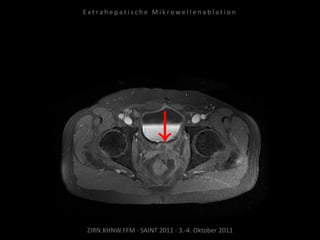

Metastase medial des linken

Musculus iliacus:

1 Nadelposition.